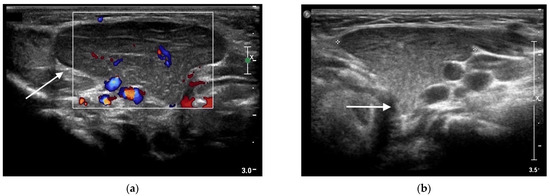

A 11-month-old toddler was referred to our Pediatric Emergency Unit for a one-week history of rhinitis and two episodes of vomiting. His prior clinical history was unremarkable. On clinical examination an acute upper respiratory infection was diagnosed, with palpable reactive bilateral cervical lymph nodes. During clinical examination a swelling located on the left submandibular area was found and an enlargement of the left submandibular gland was suspected. The swelling was painless, soft, non-pulsatile and non-fluctuating without any signs of inflammation. Blood tests were normal, showing no increase of inflammatory markers nor immunological abnormalities. A soft-tissue ultrasound of the mass was performed, showing an enlargement of the left submandibular gland, reactive lymph nodes in the left cervical area and into the parotid parenchyma, and a 3.5 × 1.7 cm hypoechoic irregular lesion, with intralesional vascular signs and punctate and linear echogenic foci resulting in a “speckled” or “salt and pepper” pattern (Figure 4a).

Figure 4.

Ectopic cervical thymus in a 11-month-old toddler accidentally noticed on clinical examination for an acute upper respiratory infection. (a) Longitudinal sonogram showing a 3.5 × 1.7 cm hypoechoic lesion (white arrow), with intralesional vascular signs and punctate and linear echogenic foci resulting in a “speckled” or “salt and pepper” pattern, compatible with ectopic cervical thymus. (b) Portion of thymic tissue (white arrow) extending into deeper layers, likely connecting the ectopic mass to the orthotopic thymus.

The echo pattern of this mass was identical to that of the normal thymus located in the superior mediastinum, thus the diagnosis of ECT was suggested. Additionally, the ultrasound showed a portion of thymic tissue extending into deeper layers, a probable remnant of its migration during embryogenesis, aiding in its identification (Figure 4b).